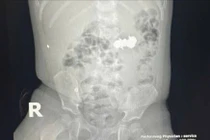

Bé trai 34 tháng tuổi nhập viện trong tình trạng viêm phổi nặng, ho khò khè kéo dài, các bác sĩ tiến hành nội soi và phát hiện thấy lòng khí quản có hình ảnh dị vật, di chuyển lên xuống trong lòng khí quản.